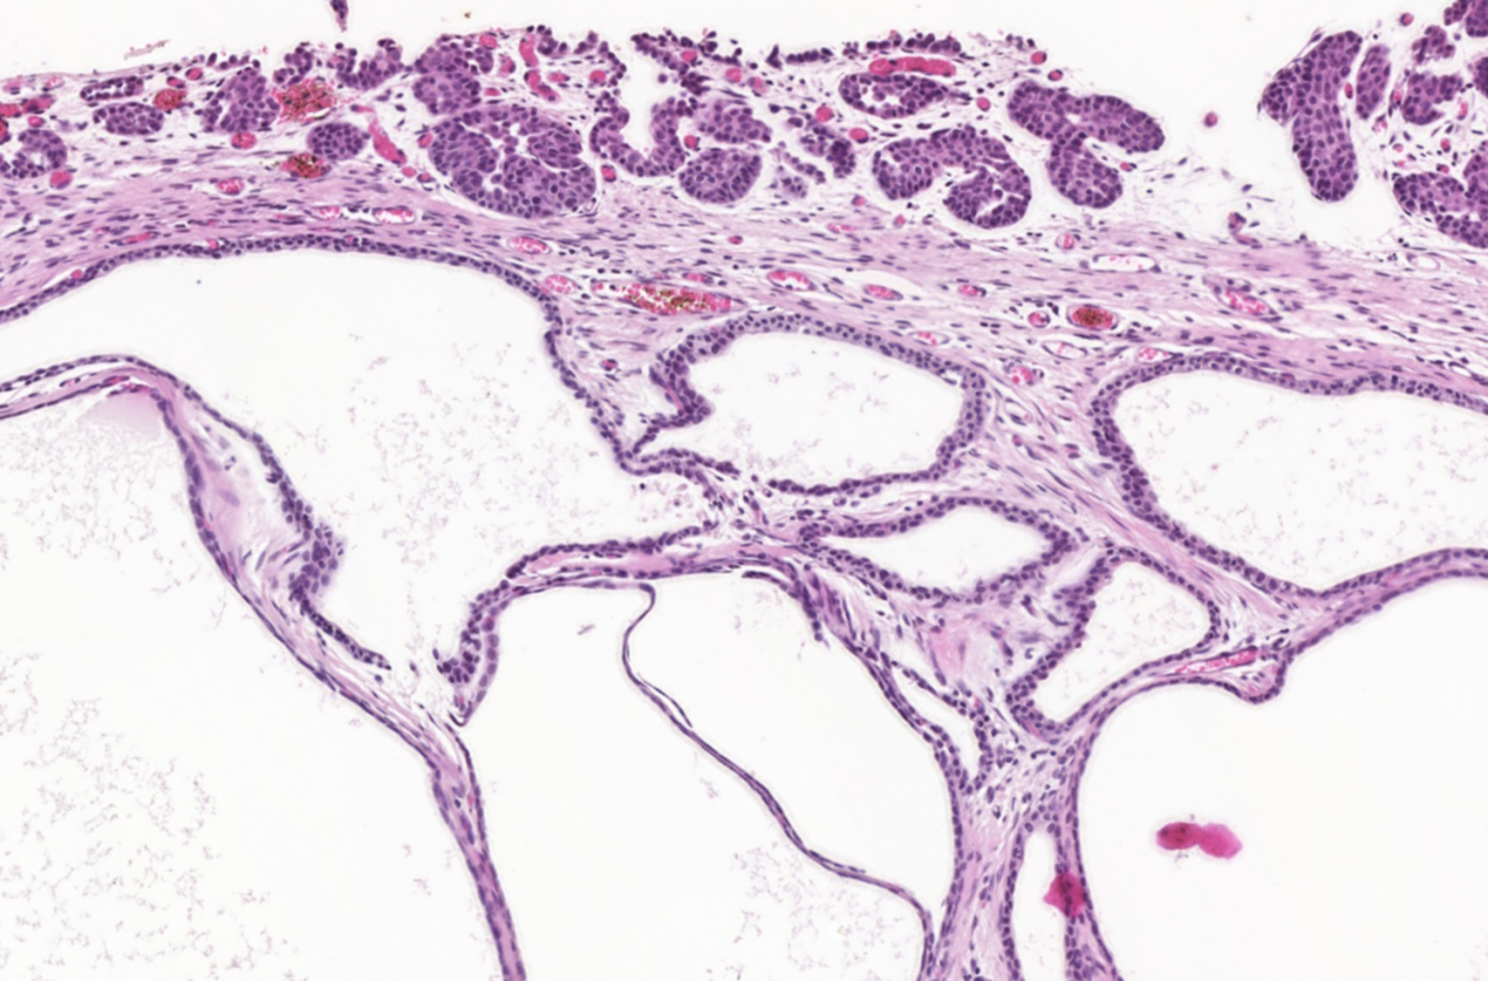

The polyps found in the bladder mucosa consist of a core of proliferative connective tissue covered by surface epithelium. This surface epithelium can form nests of hyperplastic urothelial cells in the lamina propria, known as Brunn’s nests, or undergo metaplasia to a mucus-secreting, glandular epithelial type, leading to a condition called CYSTITIS GLANDULARIS. These resulting polypoid masses may have a broad-based or pedunculated structure, occurring most frequently in the cranioventral bladder wall. Chronic haematuria, often unresponsive to antimicrobial therapy, is a common observation in cases of chronic polypoid cystitis. This bleeding is often associated with the breakdown of polyps, potentially promoting urine retention and bacterial introduction, thus establishing a cyclic pattern of infection, proliferation, and inflammation.

Histologically, our case had in lamina propria, occasionally extending from mucosa, multiple hyperplastic tortuous glands that were often cystic dilated. They were lined by one to multiple layers of uniform cuboidal or columnar epithelial cells, occasionally surrounded by a few layers of urothelial cells. They had no evident atypia. The lamina propria where they were immersed contained a few plasma cells, lymphocytes, neutrophils and rare histiocytes.